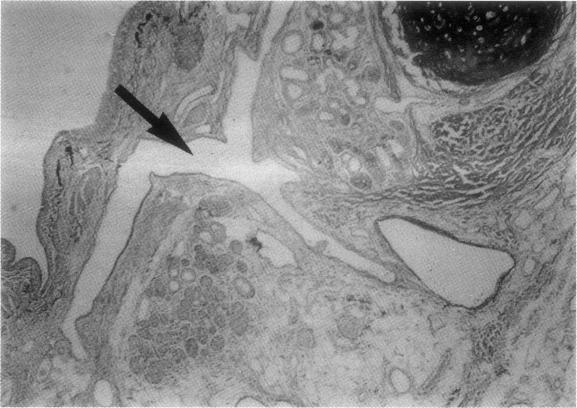

Dieulafoy's vascular malformation has not been described outside the gastrointestinal tract. Two cases are reported in which this vascular abnormality arose in right lower lobe bronchi, both of which presented with massive haemoptysis.

胃黏膜下恒径动脉破裂出血畸形尚未见发生于胃肠道以外部位的报道。本文报告两例发生于右下叶支气管的该血管异常病例,均表现为大量咯血。